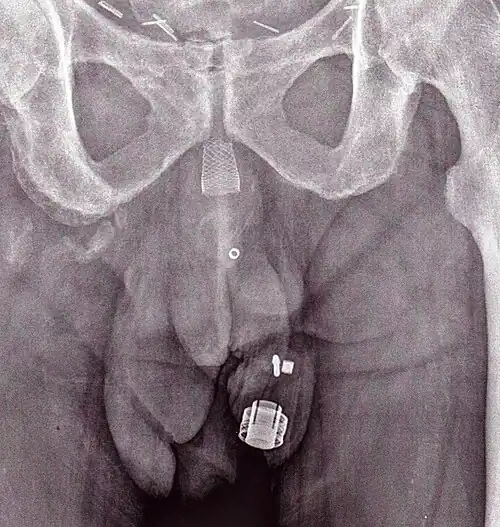

An X-ray image of implanted ZSI 375. The device is deactivated – the spring is compressed below the top of the cylinder. Patient is incontinent.

An X-ray image of implanted ZSI 375. The device is activated – the spring is decompressed at the top of the cylinder. Patient is continent.